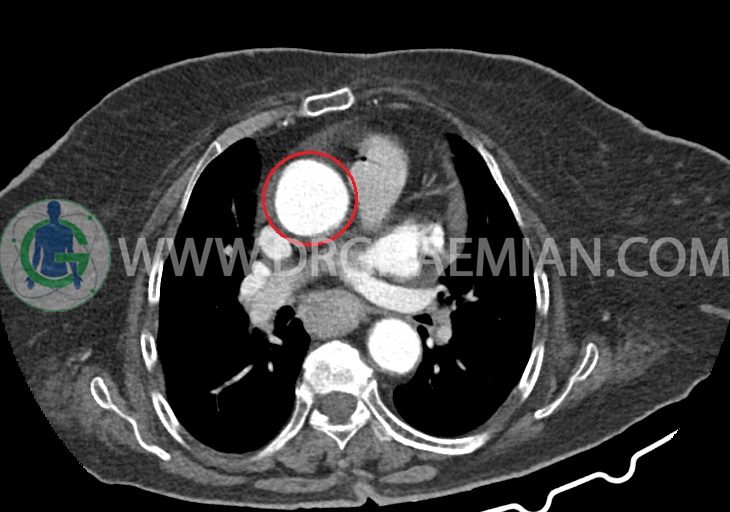

LEFT SHOULDER MRI

(Without contrast)

Technique: Axial T1 and GE , coronal T1 , T2 , sagittal T1 , T2 .

REPORT:

The humeral head has normal configuration and articulates properly and parallelism with the normally developed glenoid .

The articular surfaces are smooth and show normal cortical thickness .

The bone marrow displays homogeneous , fat – equivalent signal intensity .

The glenoid labrum is intact on all sides .

The biceps tendon appears normal and occupies a normal position in the bicipital groove.

The other muscles that cover the shoulder joint appear normal , as do imaged portions of the lungs and soft tissues .

– Complete tearing of supraspinatus tendon with grade 2 retraction and muscle atrophy

– AC joint hypertrophy with subacromial – subdeltoid bursitis

– Glenohumeral joint effusion

are seen.